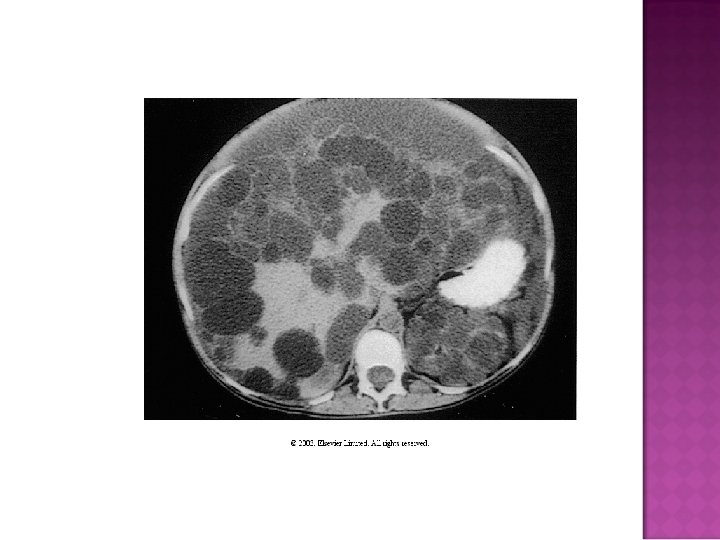

Bilateral cystic disorder in kidneys with ESRD from non-cystic disease 25 to 40% replacement of renal parenchyma CT scan or US demonstrating > 5 cysts

Incidence in ESRD patients may be > 25% Grantham and Levine report 40% incidence with 6% tumors… May occur in any patient with creatinine above 3 mg% Geographic incidence is elevated in Japan

Gross findings: overall kidney size is smaller Mean weight 76 gms Cysts may be cortex or cortico-medullary Usually less than 2 -3 cms Clear fluid, rarely hemorrhagic